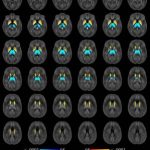

Study: Brain iron levels may predict multiple sclerosis disabilities — (Details)

A new, highly accurate MRI technique can monitor iron levels in the brains of multiple sclerosis (MS) patients and help identify those at...